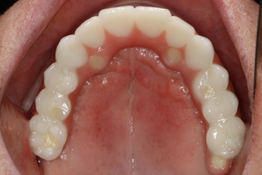

Após quatro meses, procedeu-se à cirurgia de reabertura e instalação dos pilares mini cônicos da linha de prótese do sistema CM e HI da Implacil De Bortoli e a paciente foi encaminhada para o protesista para instalação das próteses tipo protocolo. Nas figuras 9, 10 e 11 podemos observar o acompanhamento radiográfico e clínico após dois anos de follow-up.